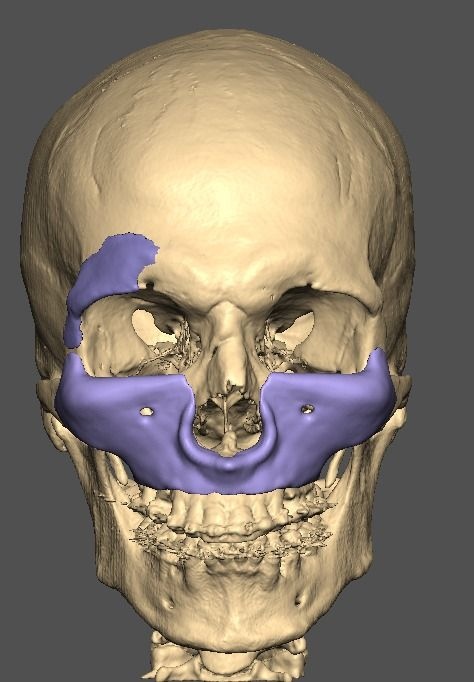

A lot changed since the initial design

It's going to be split into either 5 or 7 pieces.